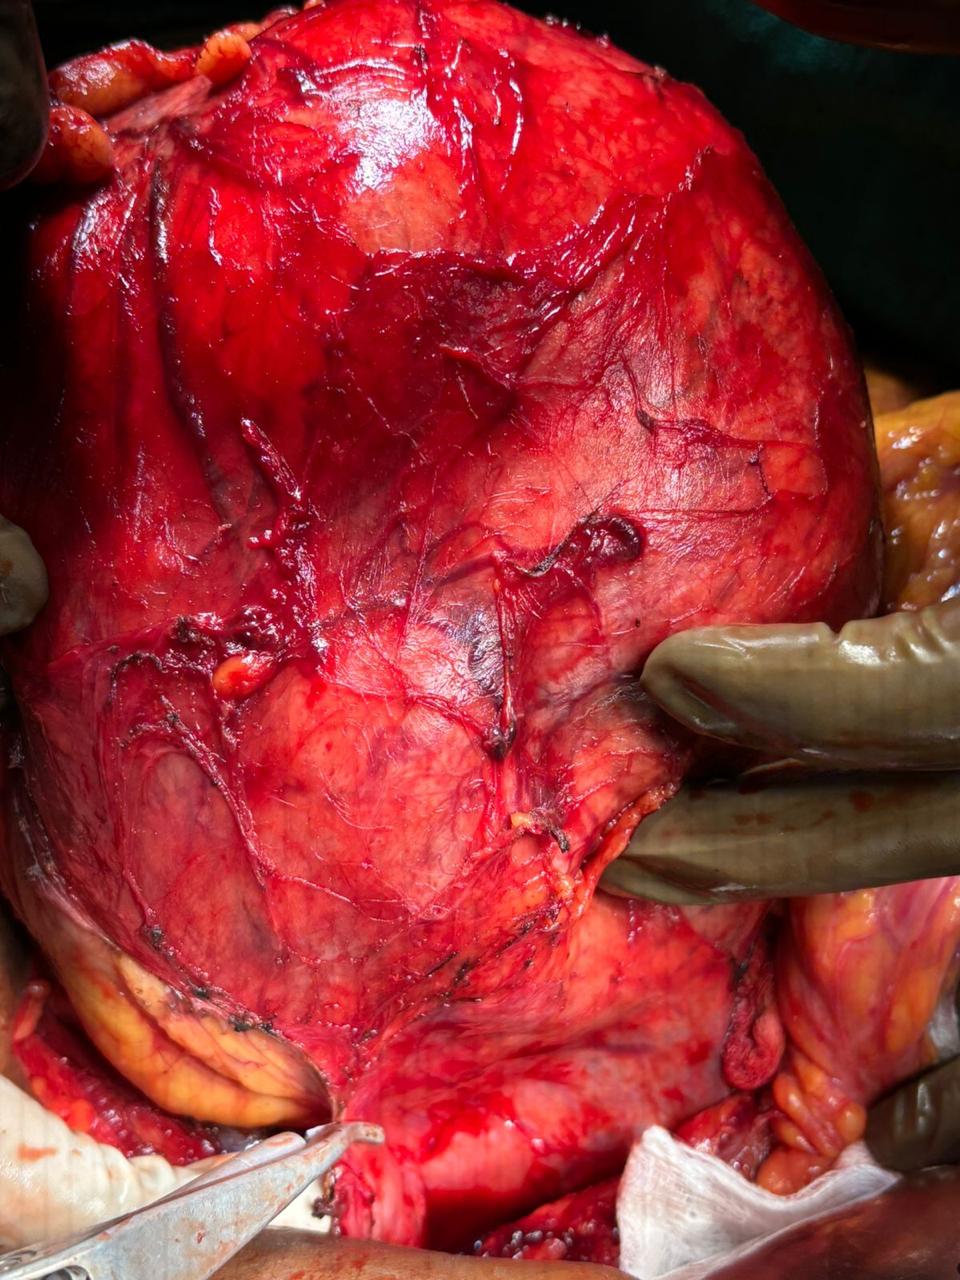

Our Gallery